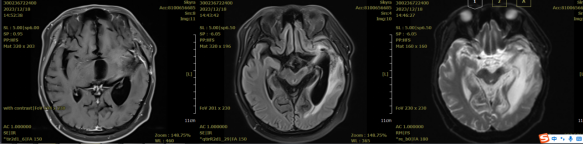

Figure 1: Before treatment, there is localized absence of the frontal, temporal, and parietal bones. Abnormal signals are observed in the left basal ganglia and left temporal lobe, which are mostly considered to indicate postoperative recurrence. Cystic lesions in the surgical area are mostly considered to be postoperative residual cavities with enhancement of the adjacent meninges in the surgical region.